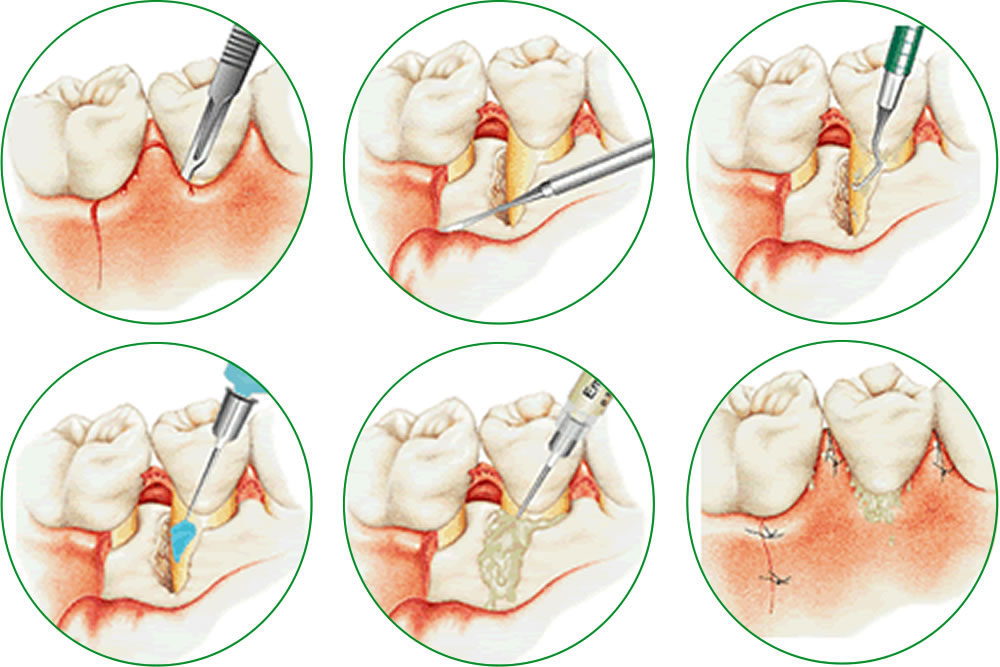

歯周病で吸収された骨を再生療法で回復

歯周病が進行すると歯を支えている歯槽骨やその周辺組織を溶かしていきます。そのため支えが不安定な歯はぐらつき、最終的には抜歯を余儀なくされます。

歯周病が進行すると歯を支えている歯槽骨やその周辺組織を溶かしていきます。そのため支えが不安定な歯はぐらつき、最終的には抜歯を余儀なくされます。

当院ではこのような症状の場合に、エムドゲインと言う薬剤を塗布して、歯周組織の再生治療を実施します。失った骨や周辺組織が修復される事により、歯のぐらつきをなくし、安定させる事が出来ます。

※エムドゲインとは、ブタの歯胚由来のエナメルマトリックス(タンパク質)が主成分の薬剤です。歯周組織再生用材料として医療機器承認を得ており、当院は国内歯科メーカーより入手しています。さらに米国食品医薬品局(FDA)の認可を受けており、世界では400万症例がある中で副作用の報告はありません。保険は適用されず自費治療となります。